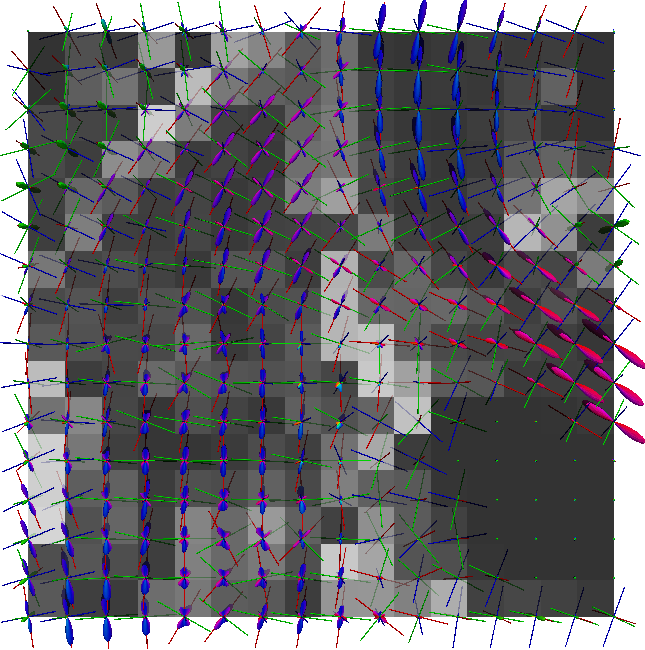

Non-negative spherical deconvolution (NNSD) (Cheng et al., 2014) is performed to estimate non-negative fiber ODFs from three-shell DWI data. NNSD works for multi-shell data. It is more robust to noise, and the obtained fiber ODFs (fODFs) in isotropic regions are closer to the isotropic spherical PDF, compared with conventional constrained spherical deconvolution (Tournier et al., 2007). After obtaining the fODFs by NNSD, the peaks are detected from the estimated fODFs with GFA larger than , as described in Section 3.4. OO and OD are calculated from the spherical harmonic representation of fODFs along their principal peaks as shown in Algorithm 1. The second row in Fig. 11 demonstrates FA from tensors estimated by DTI, OO and OD from fODFs estimated by NNSD, and the total distortion map estimated from the local orthogonal frames of fODFs. Fig. 12 and 13 show the close-up views of fODFs, local orthogonal frames, and the six proposed indices for the red and blue regions in Fig. 11, where the region shown in 12 is also visualized in the DFA pipeline in Fig. 1. The fODF glyphs are colored by using its sampled directions. The three orientations in the local orthogonal frame in each voxel are visualized by using three tubes in red, green, and blue colors respectively. There is no local orthogonal frame in some voxels because those voxels have GFA values lower than . These figures show the following: 1) OO is high in anisotropic areas with well-aligned directions, while OD is high in isotropic or crossing areas. 2) The four orientational distortion indices are low in areas with well aligned principal directions, and zero in isotropic voxels without peaks. Distortion indices are high in voxels where the principal directions in its local neighborhood change largely. 3) The central voxels in red region is the crossing area of the Corpus Callosum from left to right and Fornix that goes through the coronal slice. The twist index showed high value in this crossing area as expected.